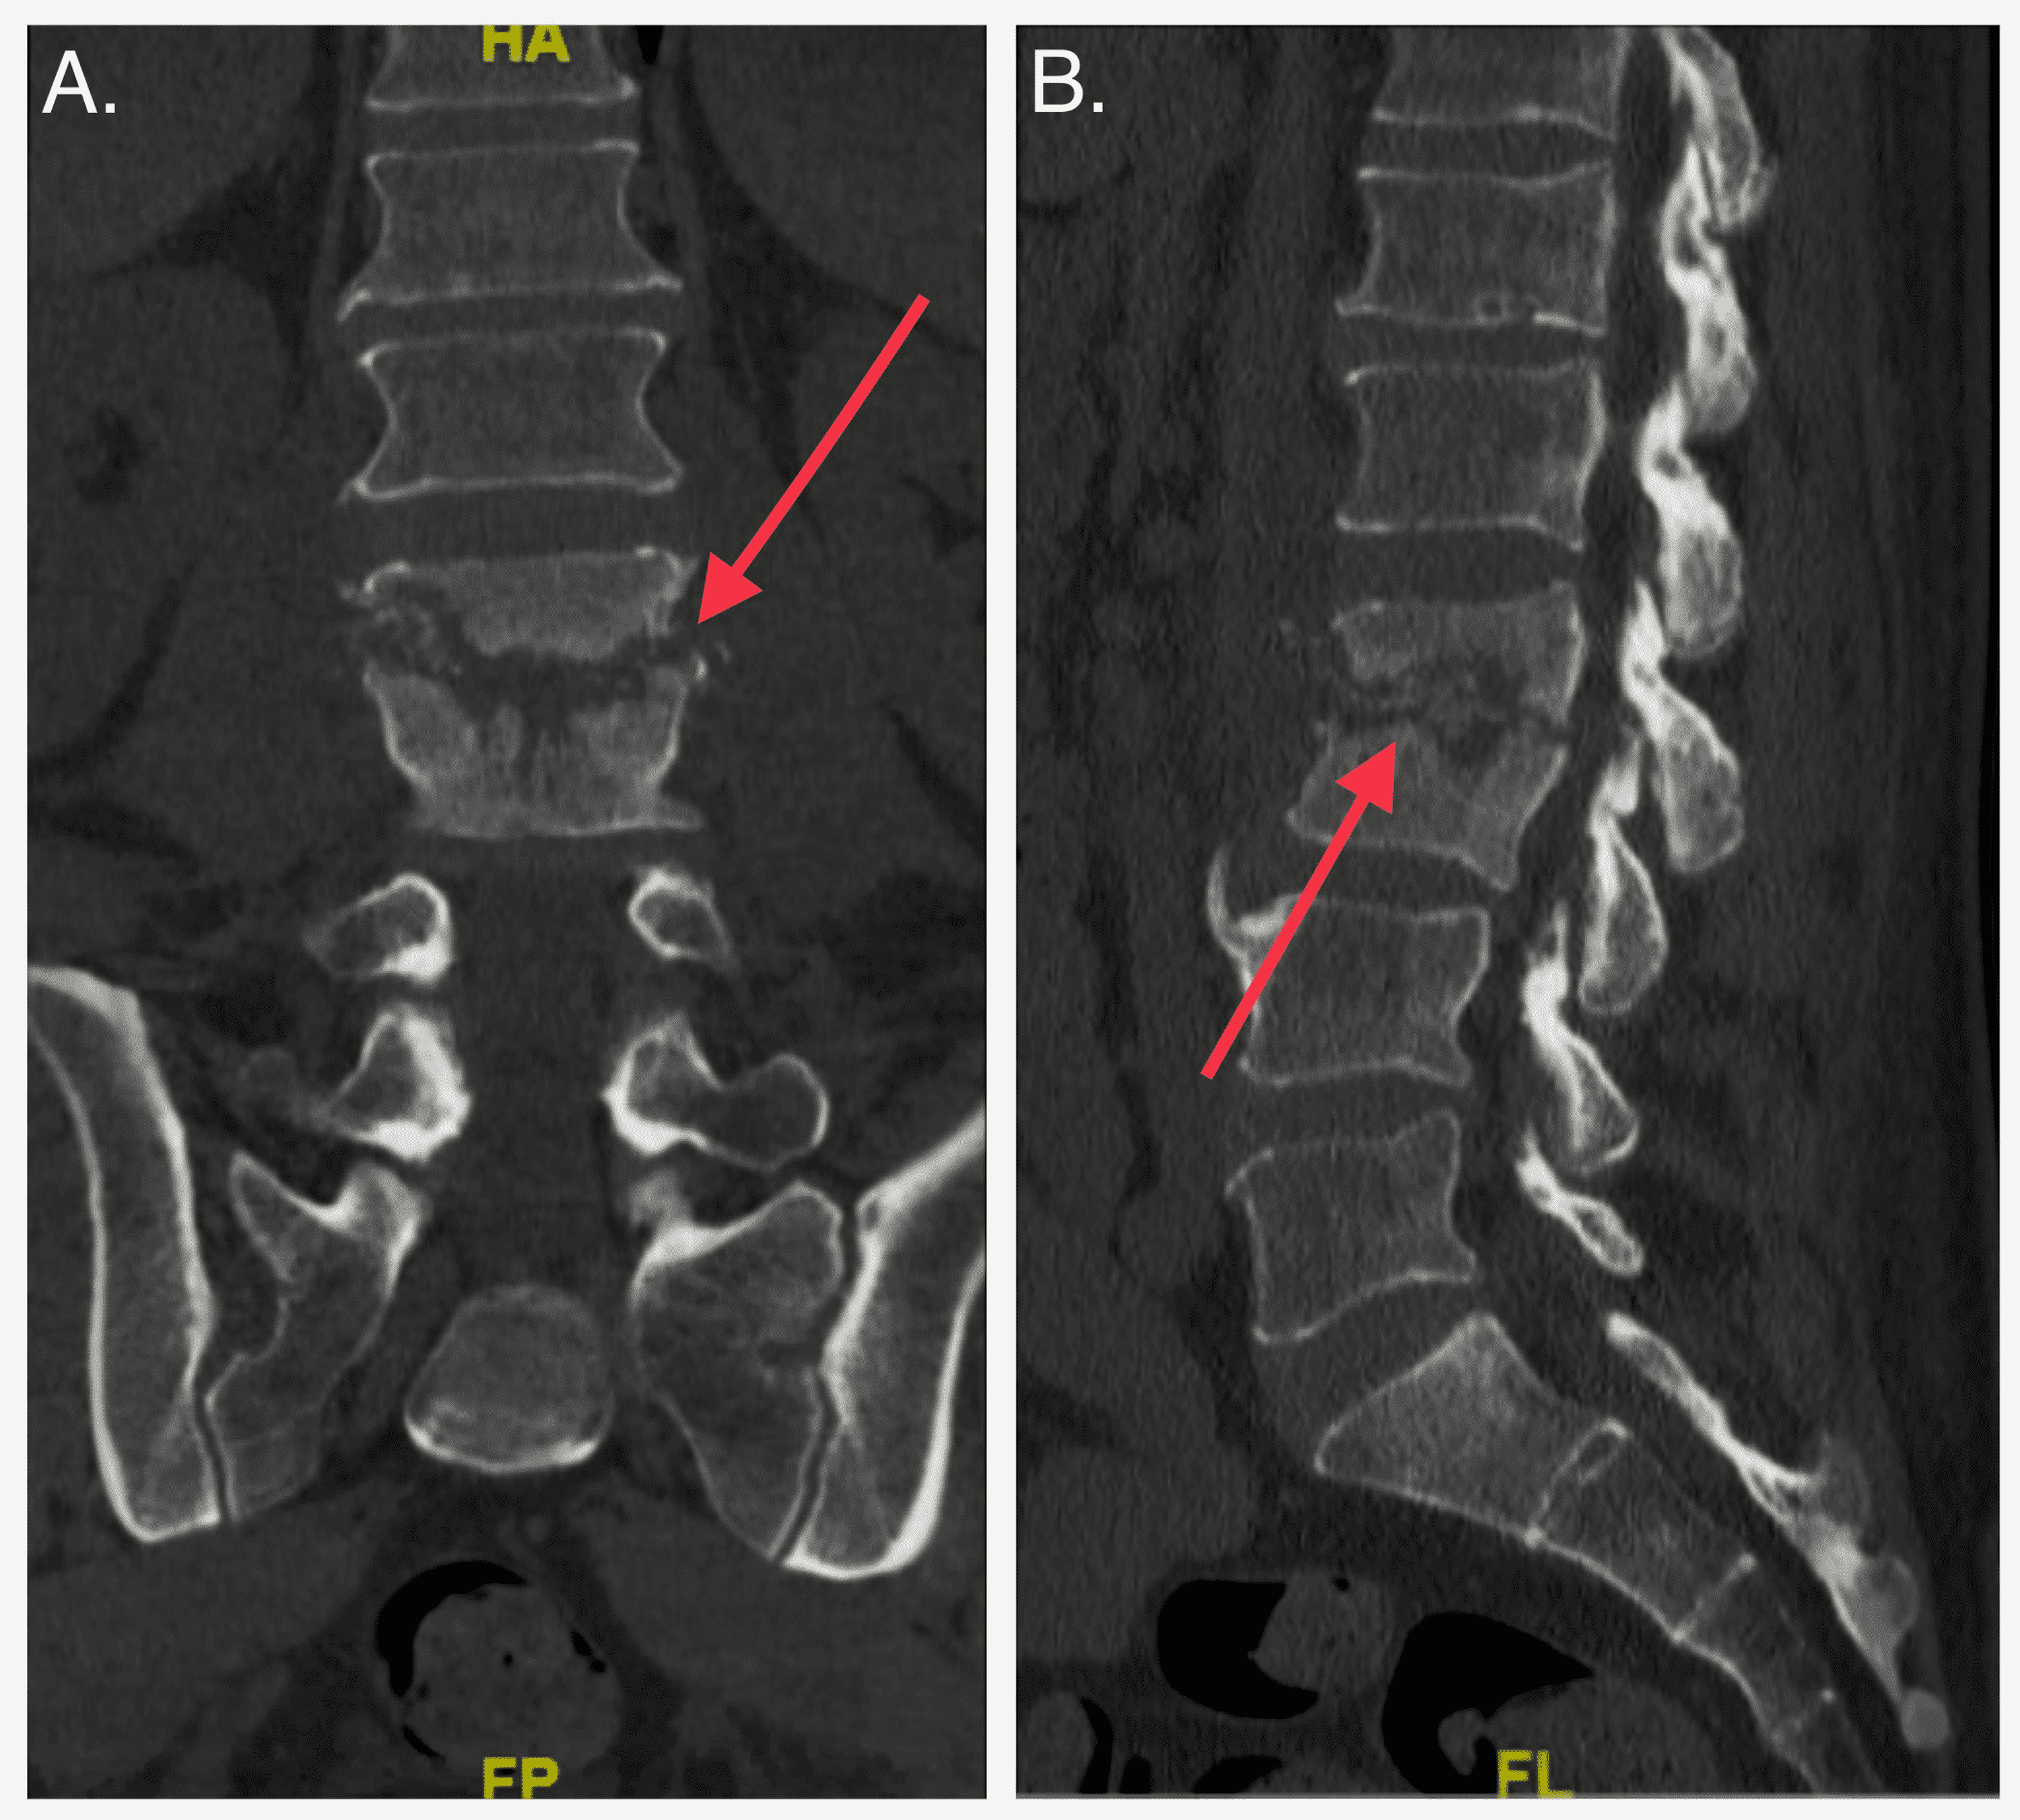

Imaging manifestations of pyogenic discitis/osteomyelitis. a Sagittal... Download Scientific What Is Osteomyelitis Discitis spread through nearby structures (contiguous spread): Osteomyelitis of the vertebral bodies and. Infections can reach a bone by traveling through the bloodstream or. osteomyelitis is an infection in a bone. vertebral osteomyelitis is usually a result of hematogenous seeding. the objective of this guideline is to improve the timely diagnosis and initial treatment of vertebral osteomyelitis,. What Is Osteomyelitis Discitis.